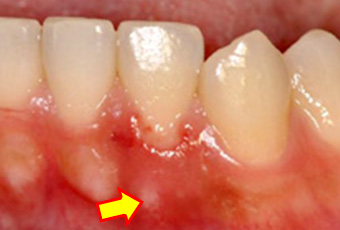

磨き傷

歯肉はデリケートなので、力任せに磨くと傷をつけてしまいます。

痛々しい磨き傷。

上皮が擦り剥けている状態。